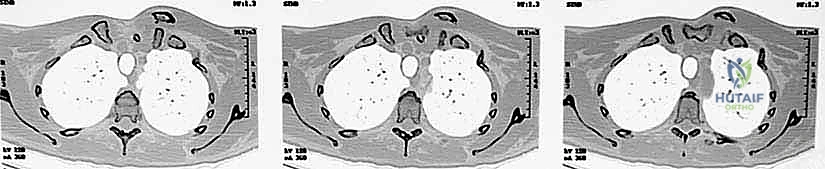

- الأشعة السينية (X-rays): يتم إجراء صور شعاعية خاصة (مثل وضعية Serendipity view). ومع ذلك، فإن الأشعة العادية غالباً ما تكون غير كافية بسبب تداخل ظلال الأضلاع والعمود الفقري مع المفصل.

- التصوير المقطعي المحوسب (CT Scan) - المعيار الذهبي: يؤكد الدكتور هطيف أن الأشعة المقطعية، خاصة مع إعادة البناء ثلاثي الأبعاد (3D Reconstruction)، هي الإجراء الحاسم. فهي تحدد بدقة متناهية اتجاه الخلع، وجود كسور مصاحبة، ومدى قرب الترقوة من الهياكل الحيوية.